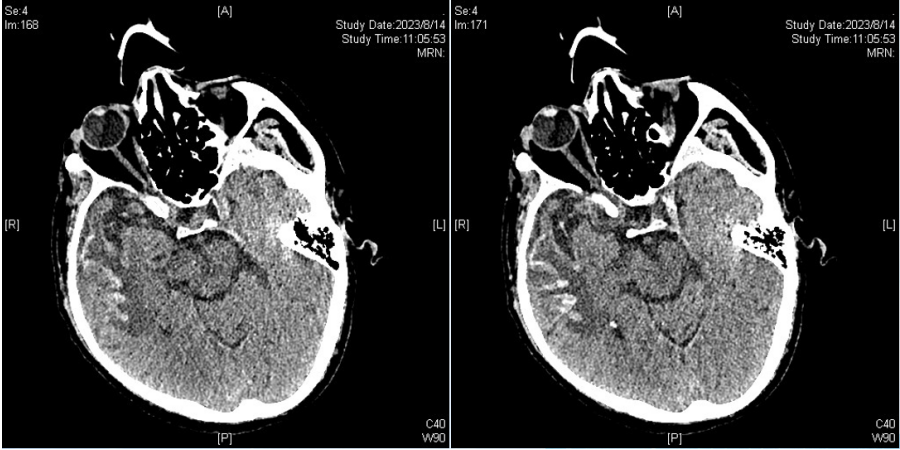

影像学

胸部CT(7月28日):双肺病变加重并出现双侧大量胸腔积液, 下肺实变和不张。

头颅CT(7月28日):右侧侧脑室、丘脑旁低密度,双侧上颌窦炎,真菌感染可能(图5)

图片

图5  头颅CT